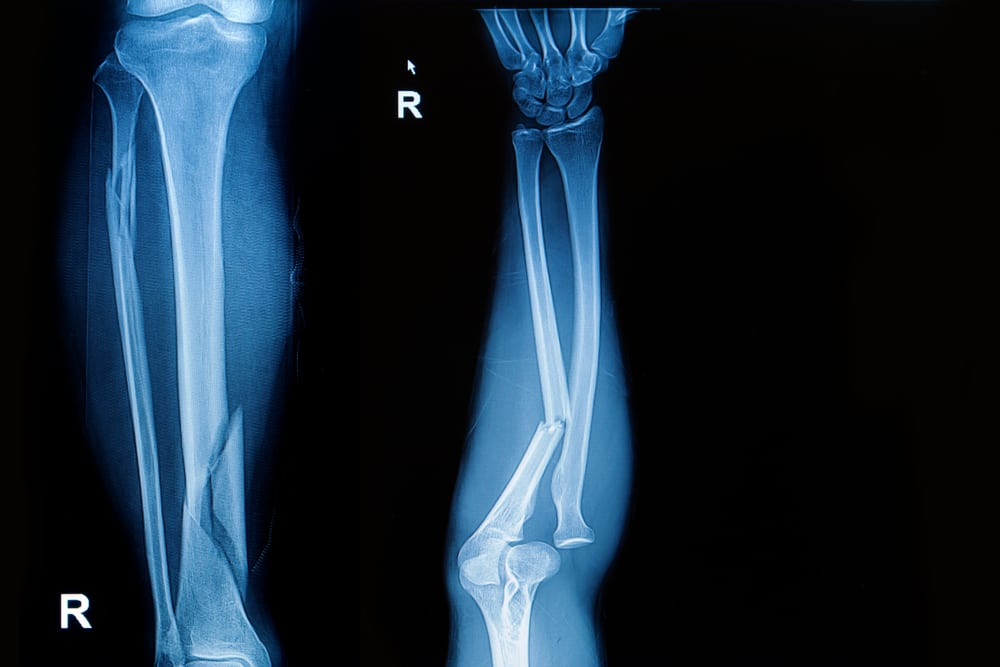

हालांकि स्पायरल फ्रैक्चर का परिणाम हमेशा हड्डी के दो अलग-अलग टुकड़े ही होते हैं। स्पायरल फ्रैक्चर के दौरान हड्डी टूटी हुई हड्डी कॉर्कस्क्रू या घुमावदार जैसी दिखती है, क्योंकि टूटी हुई हड्डी तिरछे रूप से होता है। इसे नीचे👇🏻 दिए इस चित्र से आसानी से समझा जा सकता है।

इस इमेज में बोन फ्रैक्चर के अलग-अलग प्रकार को दिखाया गया है। वहीं स्पायरल फ्रैक्चर (Spiral Fracture) के इमेज पर अगर गौर करें, तो इस फ्रैक्चर के दौरान हड्डी दो अलग-अलग हिस्सों में नजर में आ रही है। हालांकि स्पायरल फ्रैक्चर होने पर इसके अलग-अलग लक्षण भी महसूस किये जा सकते हैं।

- एक्स-रे (X-ray)- एक्स-रे की मदद से टूटी हुई हड्डी की इमेज आसानी से देखी जा सकती है और हड्डी अपनी एक्चुअल एरिया से कहां डिस्लोकेटेड हुई है इसकी जानकारी मिलती है।